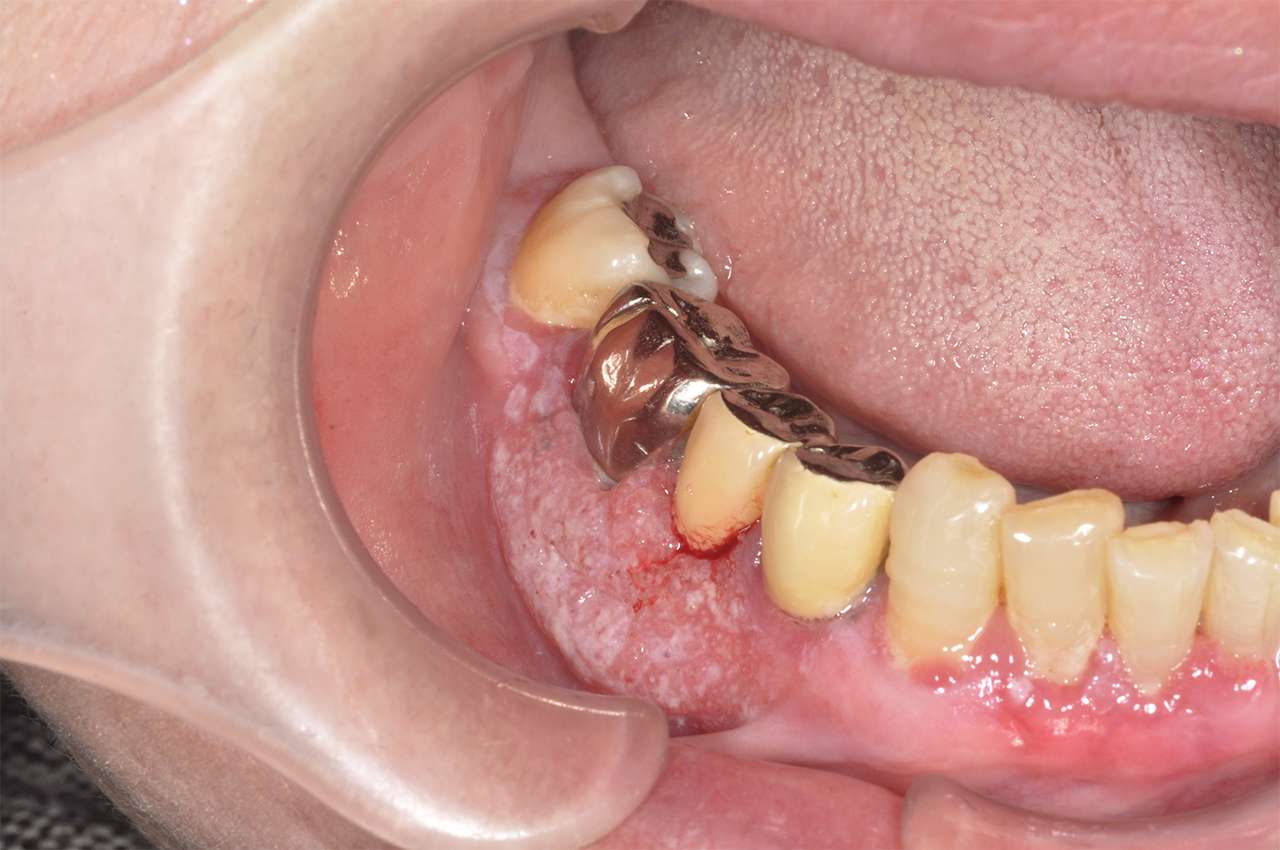

医師はさまざまな手術器具を使用して生検用の組織を収集します。口腔がんの場合、ブラシ生検として知られるタイプの組織生検がよく使用されます。

医師は柔らかい毛のブラシを使って口の病変の表面から細胞を採取し、スライドガラスに移し、特殊な染料で染色します。その後、それらを分析のために研究所に送ります。

医師はメス、ブラシ、またはその他の器具を使用してサンプルを採取します。メスを使用して切開する必要がある場合は、熱を使用してその領域を焼灼するか、または抜糸手順の必要性を避けるために溶ける縫合糸を適用します。